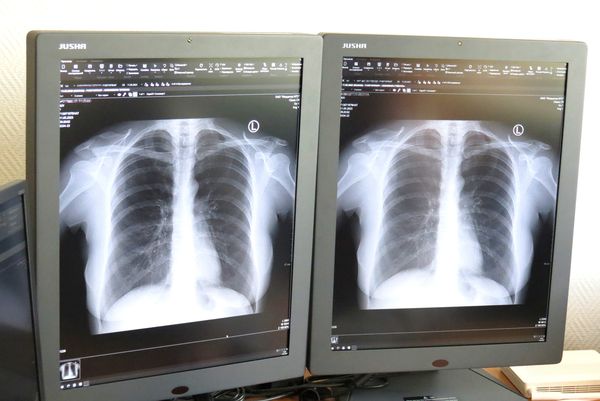

тел.+375 (17) 231- 93-26В нашем учреждении произведена модернизация рентгеновского оборудования, выполнена его оцифровка, что позволяет получать рентгеновские изображения в более высоком качестве, а так же производить запись изображений на внешние устройства( СD-диск).

Рентгенология - область клинической медицины, занимающаяся использованием рентгеновского излучения для изучения нормы и патологии органов и систем организма человека.

- - рентгенодиагностический комплекс Vision, с возможностью получения цифровых рентгеновских изображений, с записью исследования на диск в формате DICOM;

- - аппарат рентгенографический компьютерный Пульмоскан-760 – цифровая флюорография;